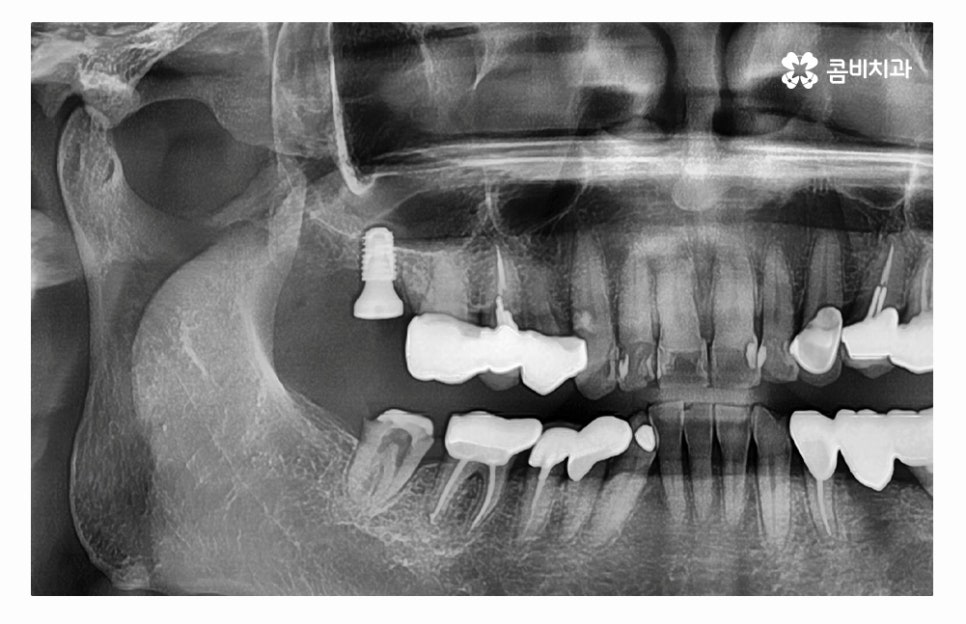

오늘 소개드릴 사례의 경우 충치로 인해 치아를 잃게 되었으며

발치 후 임플란트 수술을 통해 치아의 기능을 수복하였는데

어금니는 저작기능에서 주된 기능을 하기도 하지만

사랑니와 밀접하고 치아 사이에 이물질이 끼거나

치석이 쌓이기 쉽기 때문에 충치가 발생하기 쉬운 부위이며

나이가 들면서 보철물 교체 시기를 놓쳐 과거에 충치 치료를 했던

부위에 2차 충치가 발생되는 사례도 많기 때문에 인레이, 크라운 치료 등을

받으셨다면 오랜 기간이 지난 경우에는 검진을 받아보시고

필요시 교체를 해야 하며, 오늘 보여드린 사례와 같이

치아 속은 눈으로 확인이 어렵기 때문에 주기적인

치과 검진을 받는 것이 자연치아를 지키는 방법이라고 할 수 있어요.